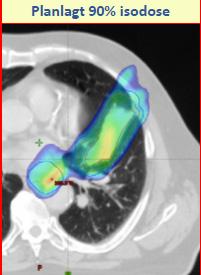

Tittelen for møtet i 2019 var Adaptiv strålebehandling - hvordan håndterer vi endringer underveis? Dette ble grundig belyst av foredragsholdere med bakgrunn som onkologer, fysikere og stråleterapeuter, fra Tromsø, Bergen, Trondheim og Oslo, i tillegg til Angela Baker, stråleterapeut fra Oxford i Storbritannia, og fysiker Ditte Sloth Møller fra Århus i Danmark. Programmet favnet vidt, med eksempler fra behandling av kreft i hode/hals, lunge, prostata og livmorhals, oppskrift på hvordan en adaptiv strateg kan implementeres, samt behov for adaptiv strategi ved protonbehandling. Det var endog et foredrag om maskinlæring, på et pedagogisk nivå som var lett til å forstå. som toksisiteten holdes uendret, eller reduseres. Det har skjedd en enorm utvikling av tekniske muligheter innen strålebehandling, både med hensyn til behandlingsteknikker og avbildingsmuligheter. «Gamle dager» med bare skjelettmatch utfra ortogonale megavolt eller kV (rtg) bilder er ikke så lenge siden, men føles nå for mange behandlingssituasjoner uansvarlig etter innføring av daglig cone beam CT på behandlingsapparatet og muligheten for bløtvevsmatch (figur 1).

Kan en del av behandlingssvikten vi ser ved for eksempel lungekreftbehandling være på grunn av suboptimal dosedekning som følge av endringer i målvolumets posisjon (figur 2)?